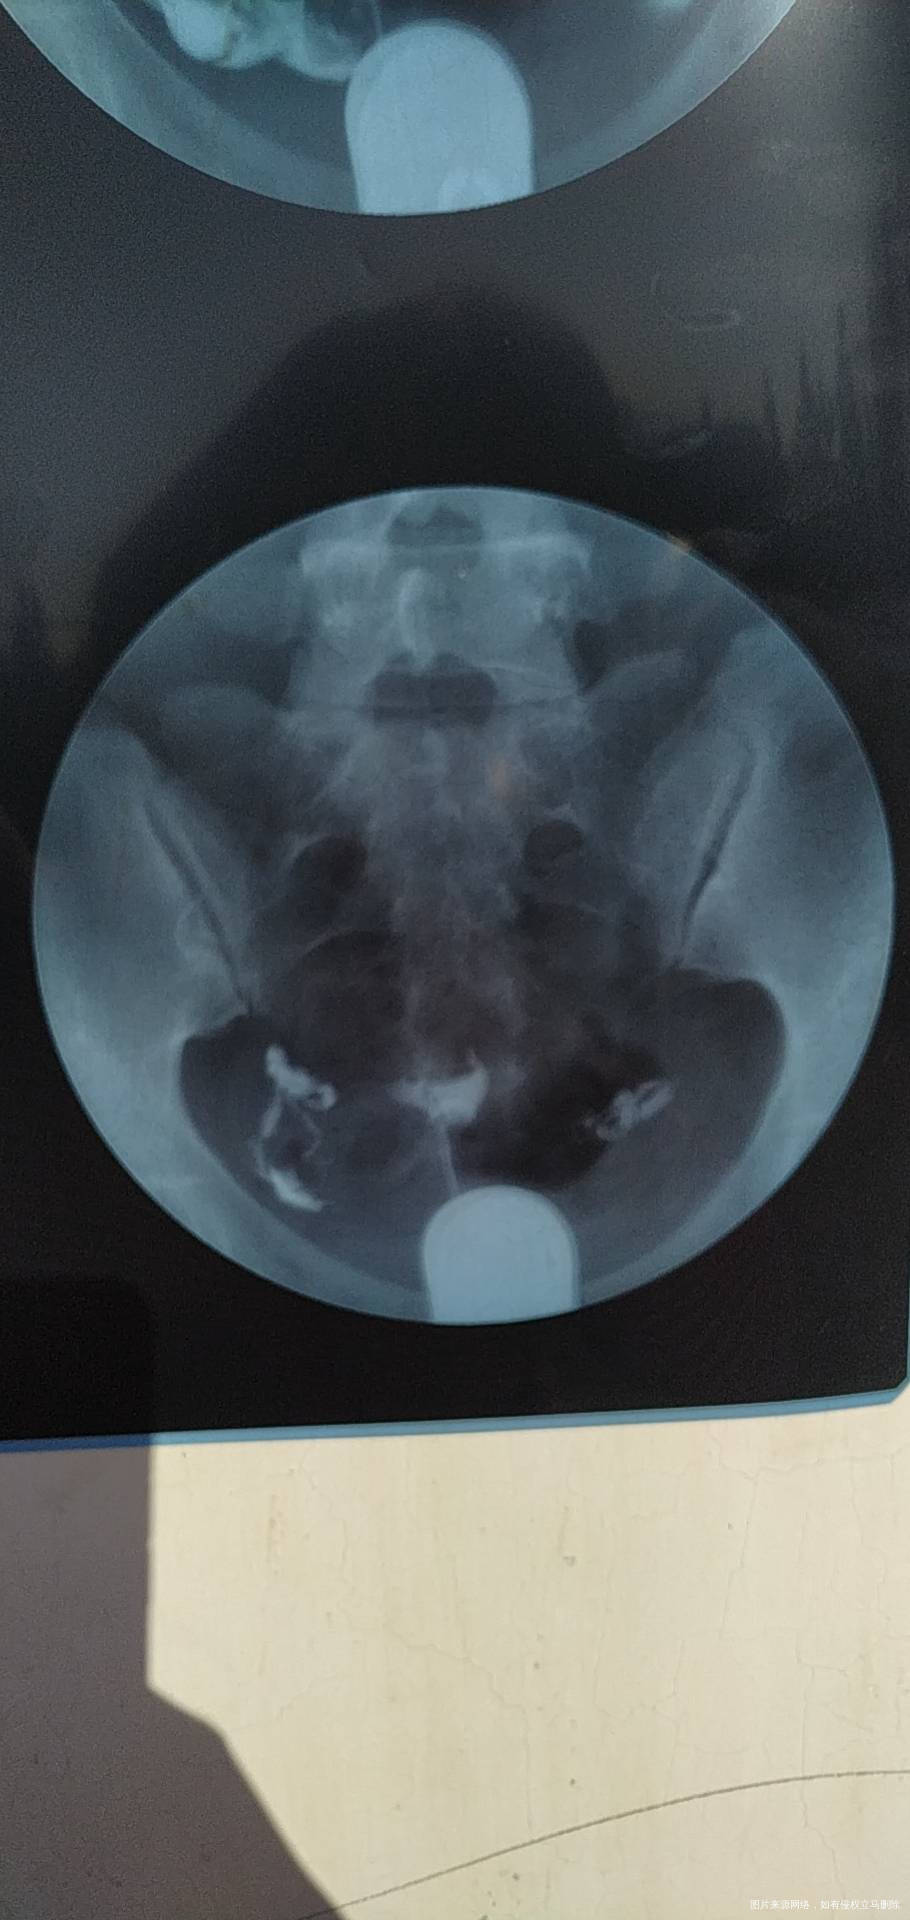

今年七月份做的造影。显示输卵管通而不畅,伴随多囊卵巢,喝中药调理了5个月,促排了两次,均失败。医生建议我直接试管,我想问一下各位专家,我还有自然受孕的机会吗?

亲,输卵管通而不畅不是代表完全不通,还是可以自己试试,多囊卵巢现在有的人太多了。你促排失败是什么原因要找找,胰岛素有抵抗吗,还是血糖油膏?这个内分没问题一般是没事,先可以深继续促排治疗